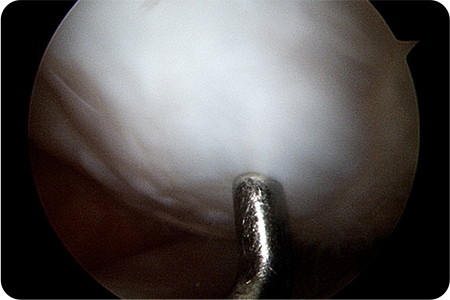

1. 관절내시경 삽입

무릎 관절 내부를 직접 확인하며 손상된 연골 부위를 관찰합니다.

2. 관절내시경 검사 및 손상 부위 정리

닳거나 손상된 연골 조각을 제거하고, 치료할 부위를 깨끗하게 다듬습니다.